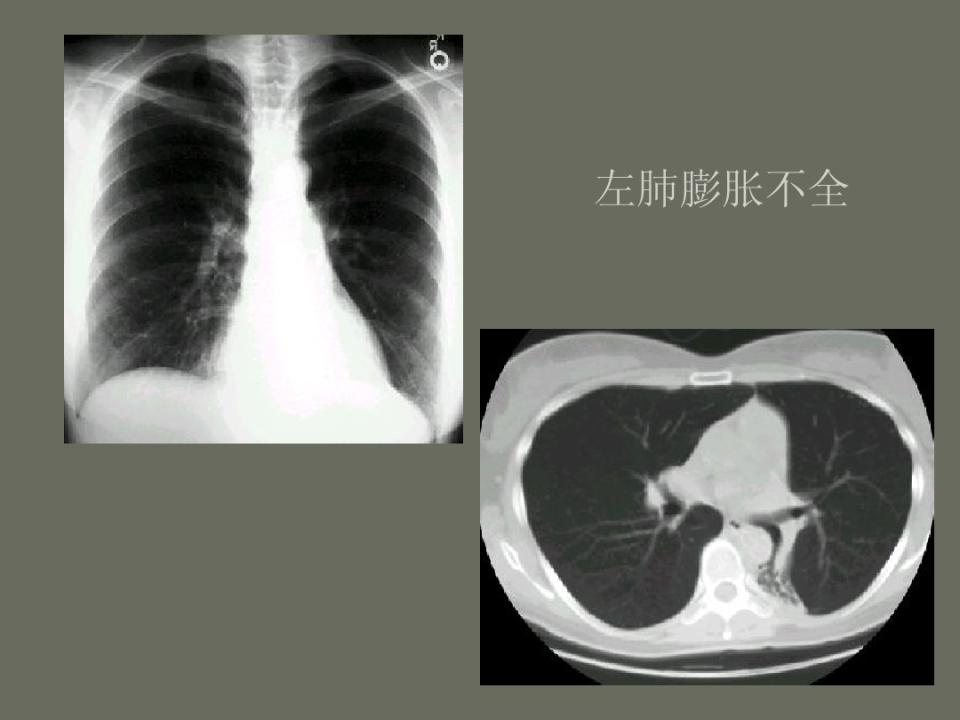

肺部先天性疾病的影像诊断